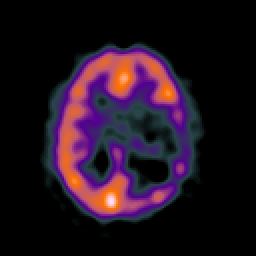

SPECT TC Study #1 -- Slice #34

[Home][Help][Clinical][Tour 1][Tour 2][Tour 3] Slice 34